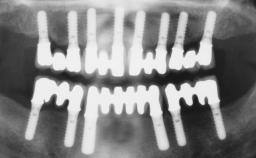

Surgical treatment of a 68-year-old female patient who experienced failure of her conventional bridge in the right maxilla. After removal of the compromised abutment teeth and a healing period of 6 weeks, a sinus floor elevation procedure using the lateral window technique and a composite graft to correct the insufficient bone height is carried out.

Two dental implants are placed in the same surgical session. The case concludes with the presentation of the final fixed dental prosthesis with a distal cantilever unit.

The 1-year follow-up radiographs demonstrate successful sinus floor elevation and stable bone crest levels around both implants, leading to a favorable long-term prognosis of the implant-supported prosthesis.